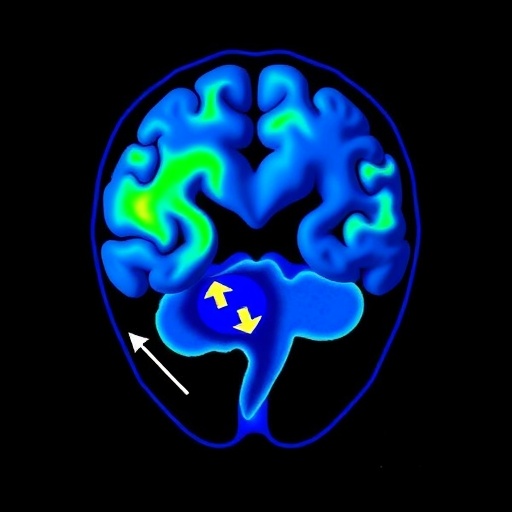

In a groundbreaking advancement at the crossroads of neuroscience and artificial intelligence, researchers have unveiled an innovative approach to understanding the aftermath of hypothalamic hamartoma (HH) surgery through multimodal contrastive learning applied to resting-state functional MRI (rs-fMRI) data. This new technique reveals subtle yet significant changes in the brain’s functional networks, offering promising insights into whole-brain network recovery—a feat that traditional neuroimaging analyses have long struggled to achieve.

Hypothalamic hamartomas, congenital malformations located near the hypothalamus, are notorious for inducing severe epilepsy that frequently resists pharmacological treatment. Surgical removal of HH is often the only viable option to control seizures but assessing how this intervention affects brain-wide network function has posed a formidable challenge. Conventional rs-fMRI analyses encounter limitations in detecting minute but critical shifts in the complex interplay of neural circuits post-surgery, obscuring a full picture of cerebral recovery.

Addressing this challenge head-on, a team led by Jeyabose and colleagues developed a sophisticated two-stage contrastive learning algorithm capable of discerning intricate network changes by integrating multi-dimensional rs-fMRI data. This approach uniquely combines spatial and temporal information—specifically three-dimensional Independent Component Analysis (ICA) maps with one-dimensional ICA time series—allowing the model to encode rich, multifaceted representations of brain activity before and after surgery.

Visual inspection of the learned feature space via t-distributed stochastic neighbor embedding (t-SNE) revealed stark separation between pre-surgical and post-surgical brain states. This clear delineation across all five examined networks underscores the model’s capacity to identify functional reorganization induced by surgical intervention—a milestone in neuroengineering that bridges computational sophistication with clinical applicability.